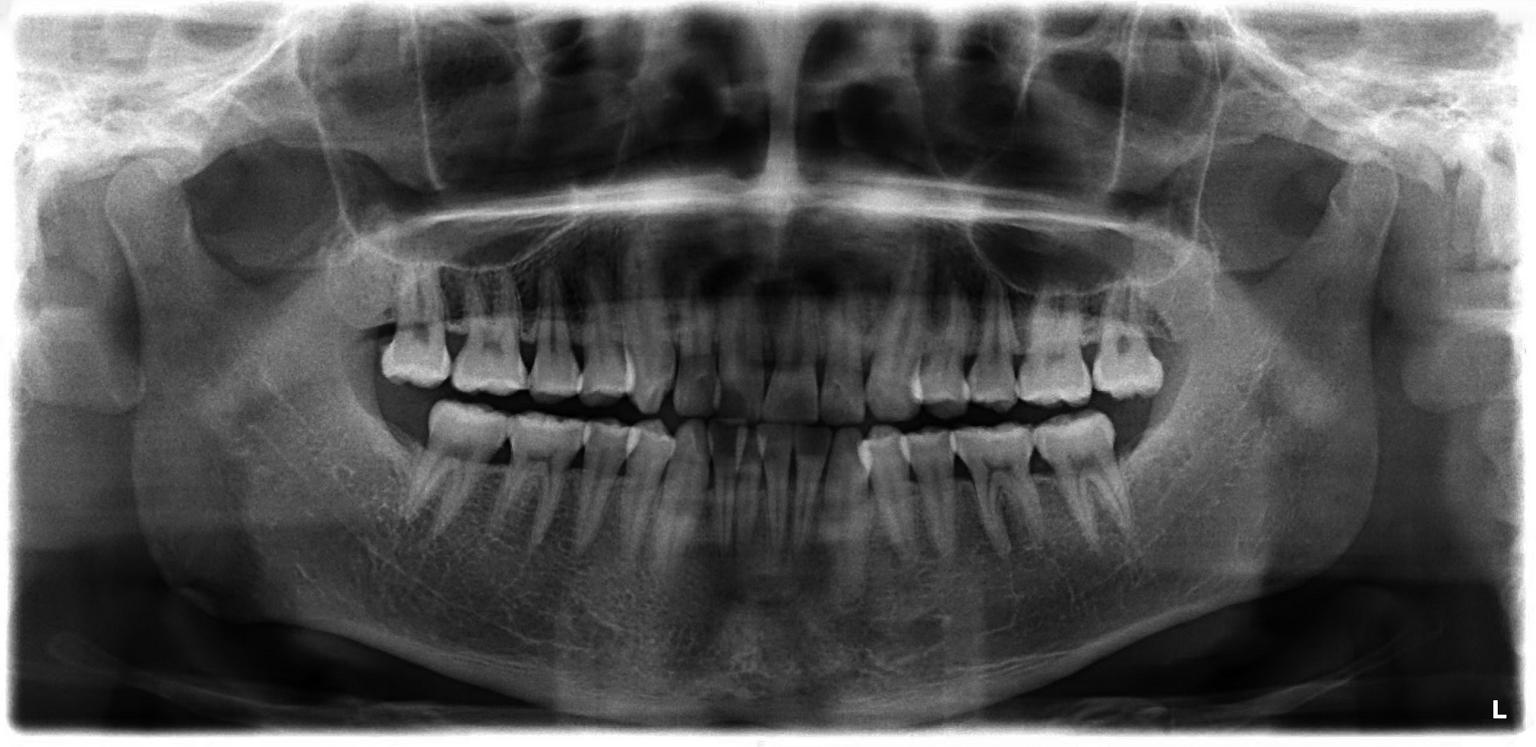

在为口腔癌患者制订治疗计划时,医生需要考虑到牙齿和颌骨这两个因素。全景片,也称“全颌曲面断层片”,能够显示全口牙齿和上下颌骨,可以直观地了解口腔癌患者的口腔内牙齿整体情况,尤其是龋齿、残根及智齿等,为治疗计划的制订,特别是牙齿的处理方案,提供直观的依据。此外,全景片还可以显示鼻腔、上颌窦及颞下颌关节等解剖结构,能够大致观察口腔癌对颌骨组织是否有影响以及影响程度,辅助医生判断是否需要切除颌骨组织及切除的安全范围。全景片是二维的影像检查,操作简单、辐射剂量很小、价格便宜,是临床上口腔癌诊疗的基础检查手段之一。